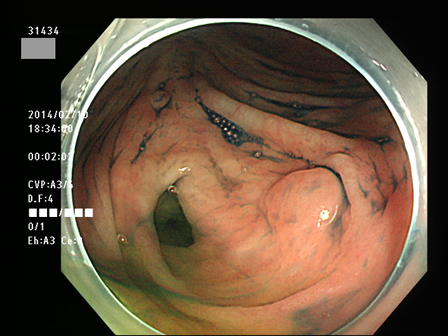

上記100名より抽出した平坦・陥凹型腺腫(=癌化の危険が高いが見落としやすい病変)の内視鏡写真